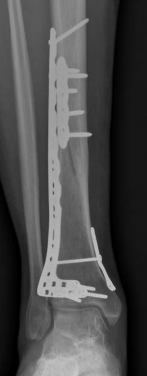

Complex Tibial Shaft Fracture: Plate Fixation for Plafond Extension

We review everything you need to understand about Complex Tibial Shaft Fracture: Plate Fixation for Plafond Extension. A **tibial shaft fracture** extending into the plafond is a complex injury characterized by a displaced, often multifragmentary break in the midshaft of the tibia that also involves the ankle joint's articular surface. These severe fractures commonly require immediate fasciotomy if compartment syndrome is present, followed by open reduction and internal fixation (ORIF) to restore anatomical alignment and joint function.

When a diaphyseal fracture propagates into the distal articular block, the injury transcends the typical treatment algorithms reserved for isolated tibial shaft fractures. Intramedullary nailing, the gold standard for diaphyseal fractures, becomes fraught with complications such as articular malreduction, propagation of intra-articular fracture lines, and inadequate distal fixation. Therefore, plate fixation—often utilizing minimally invasive percutaneous plate osteosynthesis (MIPPO) techniques—emerges as the primary definitive treatment modality. In the setting of an AO/OTA 43C3.3 fracture, where the articular surface is multifragmentary and completely dissociated from the diaphysis, the surgeon must meticulously reconstruct the joint surface before bridging the diaphyseal segment.